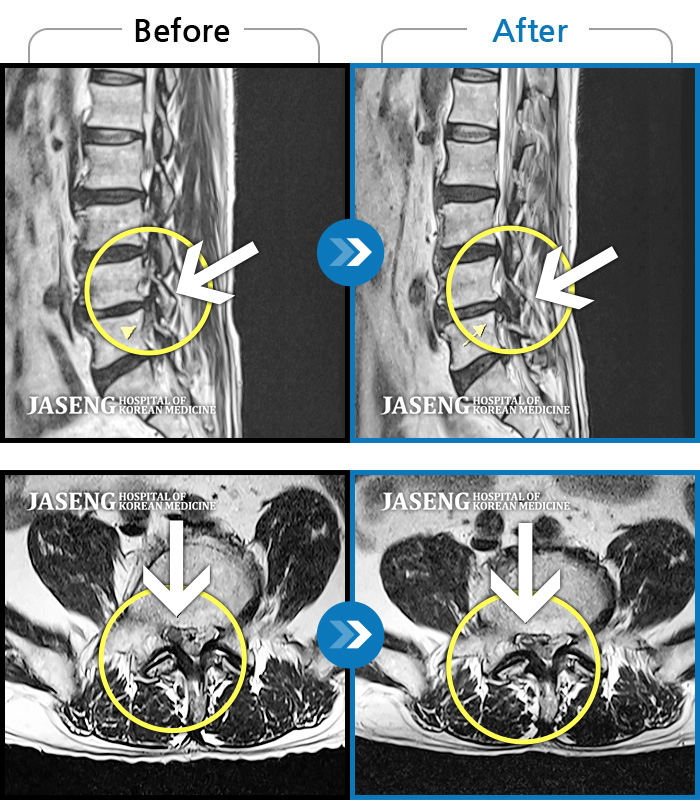

허리디스크

광주 · 김동은 원장

허리 통증과 양측 둔부부터 허벅지, 발목 부위 저리는 증상으로 내원하셨습니다.

촬영시기

2025.05.09 ~ 2025.12.18

요추 5번과 천추 1번 사이에서 탈출된 디스크가 신경막을 압박

2017.08.26 ~ 2018.03.31